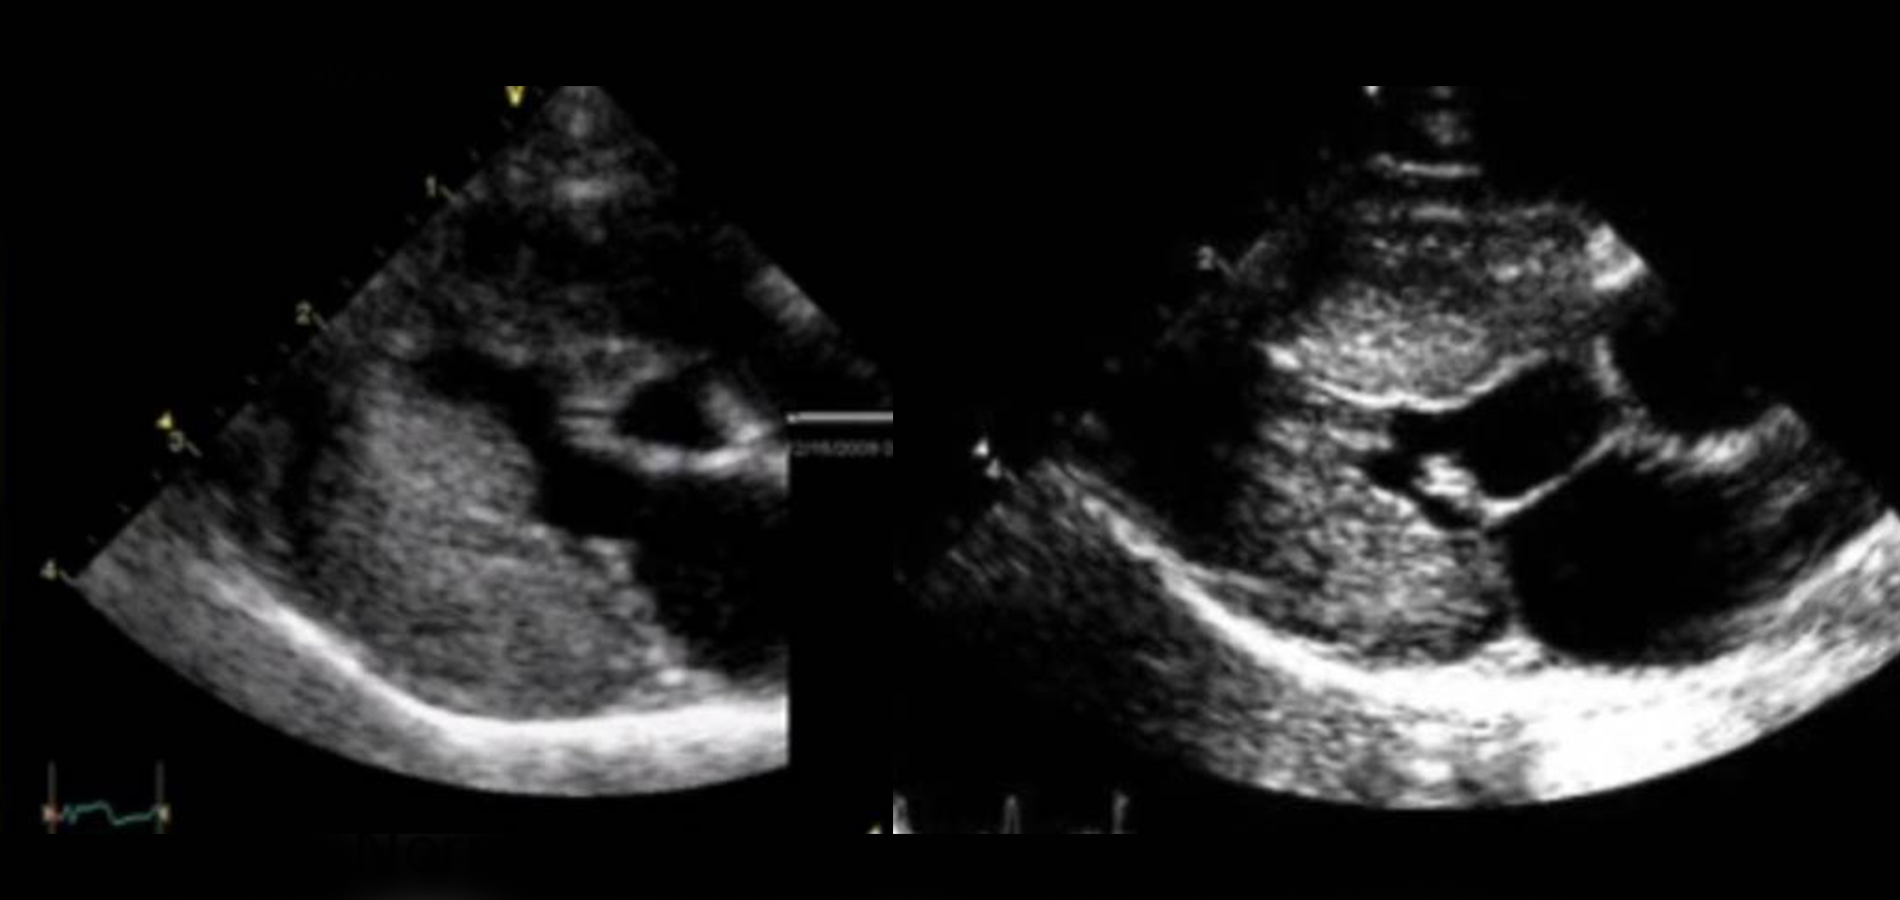

Окончательный диагноз ставится на основании ультразвукового исследования сердца (ЭХО КГ).